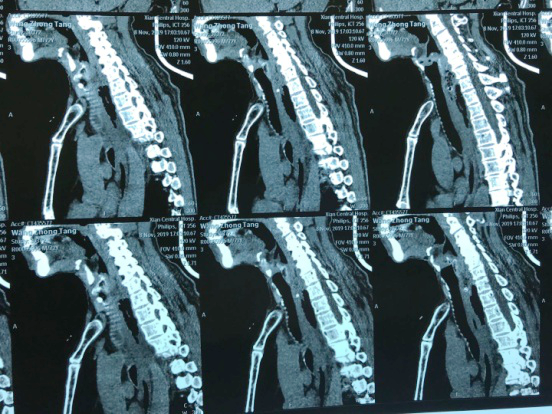

“大夫,快,我这人卡枣核5天没吃饭了,县医院说枣核又往下掉了”,2019118日下午,一位72岁老人在一群家属的搀扶下来到按摩视频 耳鼻喉科门诊,门诊医师刘飞接诊患者询问病史,原来老人在村里“坐席”不慎将枣核误吞,在村卫生室、县城医院等多家医疗机构就诊,未能取出枣核,考虑枣核位置不断下移,建议转上级医院。至此患者因咽痛无法下咽已经5天滴水未进。患者既往糖尿病、冠心病,且未规范药物治疗,基础条件很差。考虑患者病情危重,予以迅速办理入院。权博源主任医师和尹黎波主治医师详细询问病史及查体后,为患者急查血:白细胞22,血糖、血酮、尿酮高,凝血象报危急值。患者食道异物食道穿孔合并严重感染,长期饥饿合并高血糖,手术风险很大。权博源主任医师亲自为患者制定治疗方案,立即抗感染、补液治疗,请内分泌科协助降糖降酮治疗,同时复查CT确定枣核现在位置,指标控制后立即手术。晚上10点,在麻醉科、手术室紧张有序的配合下,终于将枣核和覆盖在上方的鸡蛋样异物取出,术后患者平稳返回病房。